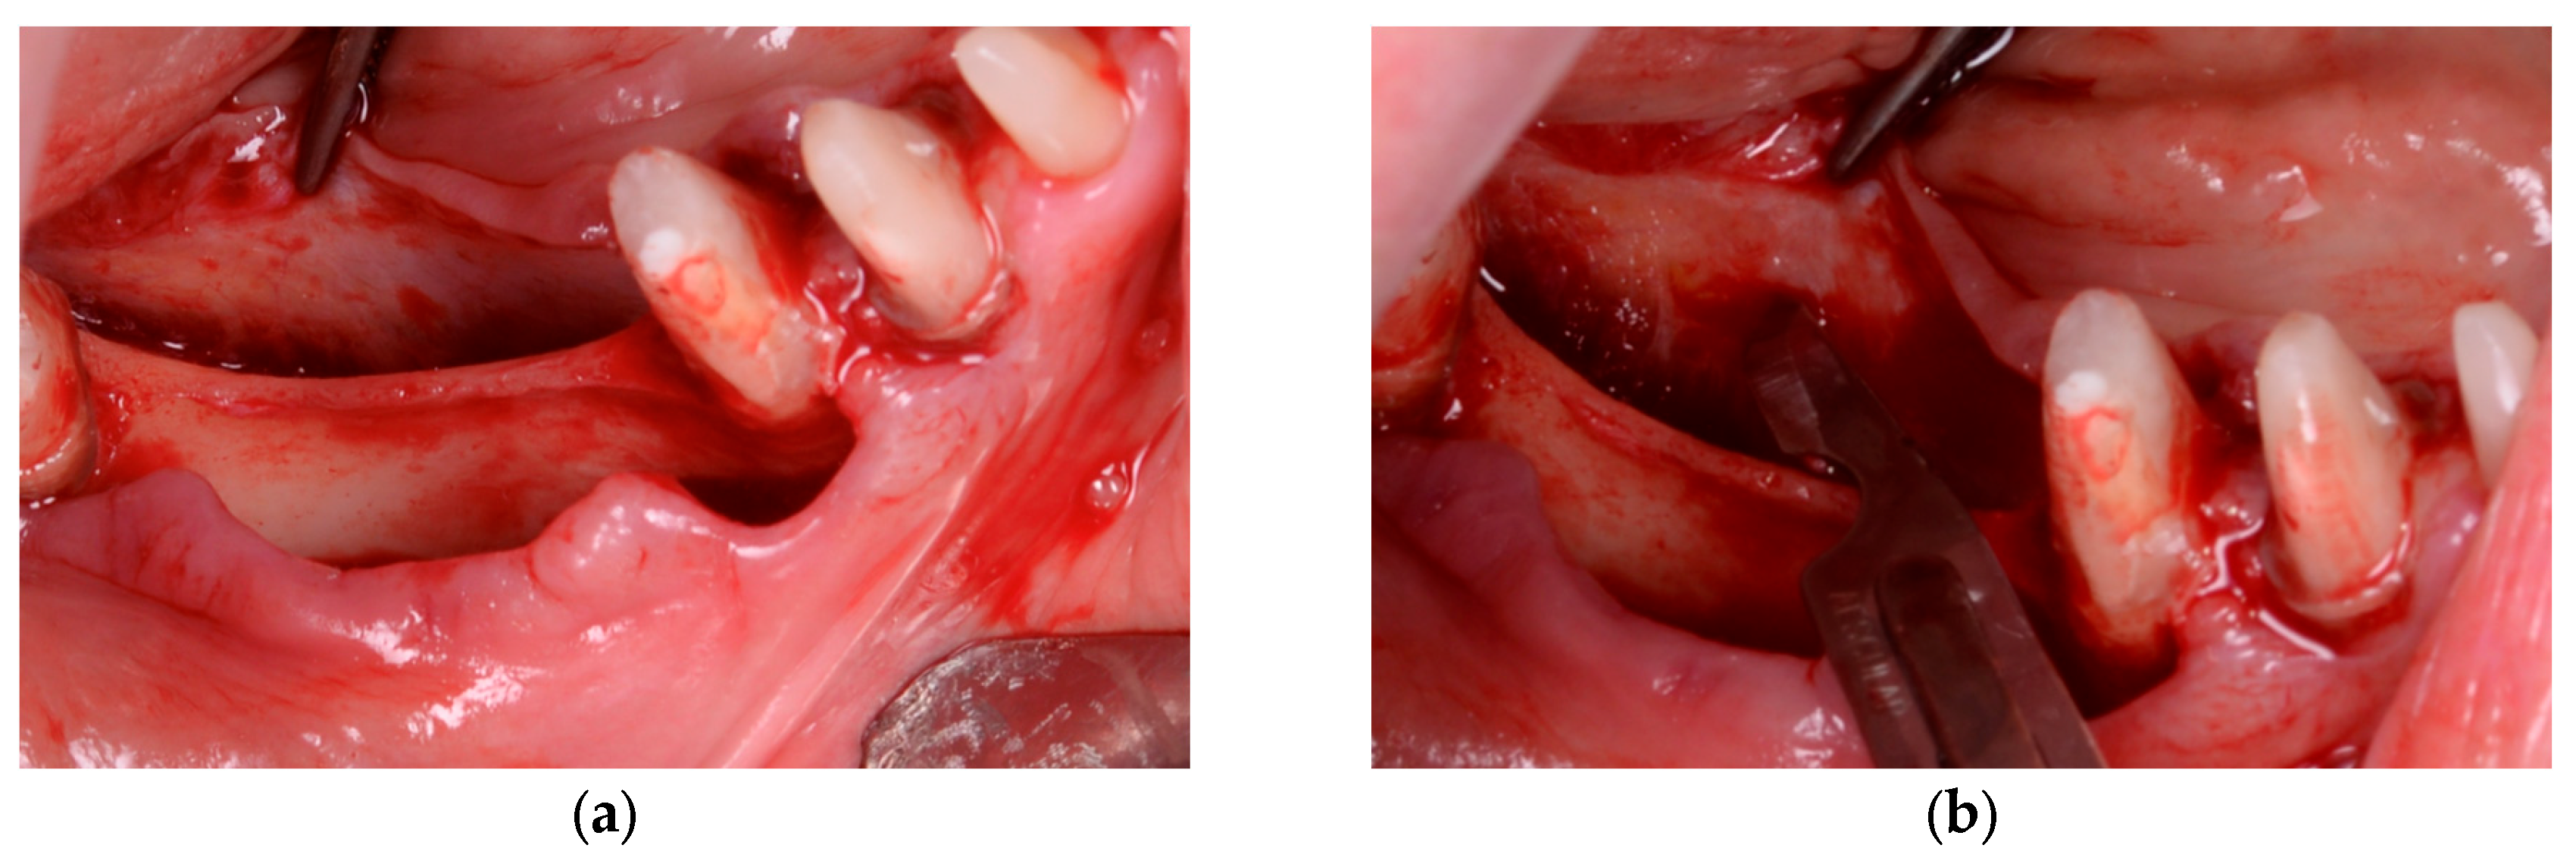

In Group B (PRF + Composite Graft + Collagen Membrane), the bone defects were filled with a composite graft consisting of 70% allograft and 30% xenograft, covered with a resorbable collagen membrane (Biomed Extend, Zimmer Biomet, Warsaw, IN, USA). Before flap closure, multiple layers of autologous PRF membranes were placed over the membrane to enhance vascularization, support graft integration, and reduce postoperative inflammation, as illustrated in Figure 3 and Figure 4.

Figure 3. (a) Initial clinical view of the bone defect. (b) Placement of the bone graft composed of 30% xenograft (Bio-Oss®, Geistlich Pharma AG, Switzerland) and 70% allograft (Puros Cancellous Particulate Allograft, ZimVie, Germany). (c) Application of a resorbable collagen membrane (Biomed Extend, Zimmer Biomet, Warsaw, IN, USA) over the grafted area. (d) Stabilization of the grafted site using vertical mattress sutures with resorbable material (Chirmax 5-0 DS15, Chirmax, Prague, Czech Republic), prior to final positioning of the PRF membranes.